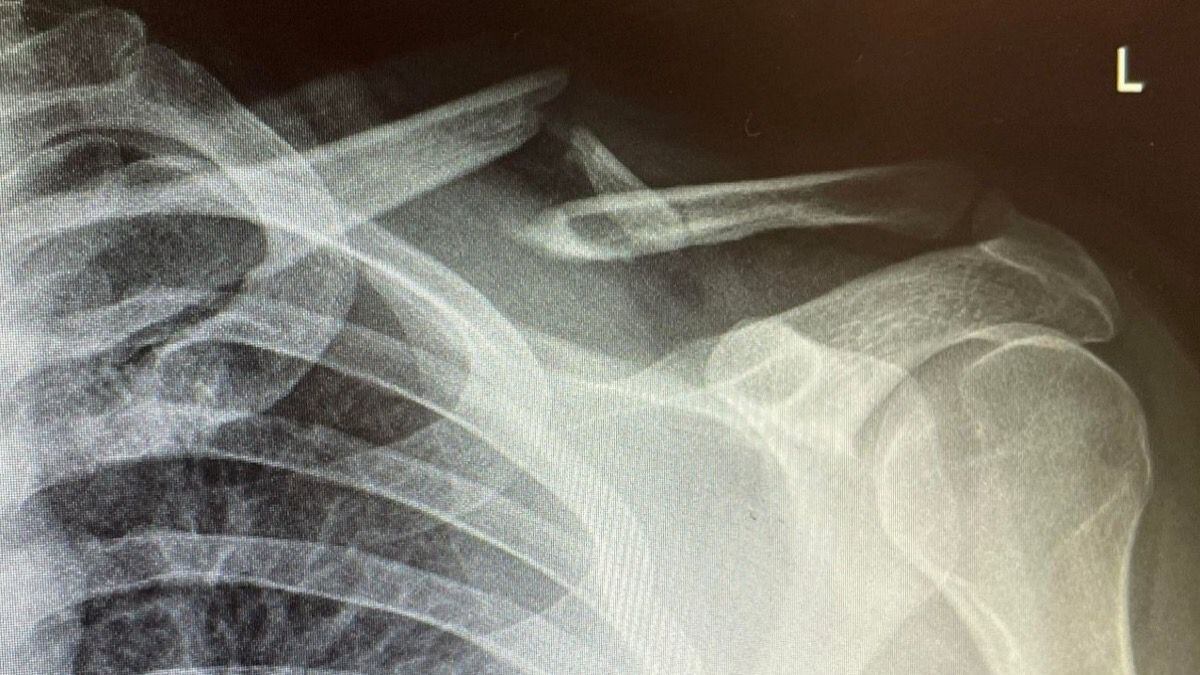

Luego de dirigirse a un centro hospitalario, se pudo establecer que Skill Specs tenía rota la clavícula en tres partes. Por medio de su cuenta de Twitter el mismo streamer mostró a sus seguidores la radiografía donde se evidencia la lesión.

“Tuvieron que abrir el cabr** y agregar una viga de soporte (...) El descanso más doloroso que he tenido, de vuelta a casa y sintiéndome como un imbé**”, señaló Skill Specs en su cuenta de Twitter.